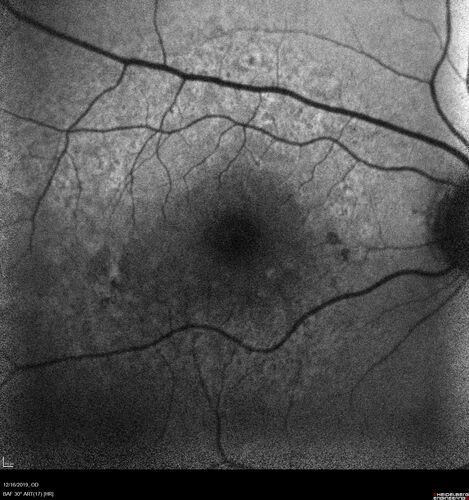

Intermediate Dry Age-Related Macular Degeneration - Soft Drusen

70-year-old Left eye worse than the right.  Both eyes see distortion in the amsler grid for a few months

HTN, High Lipids, Osteoporosis

Meds: Lutein once daily, Calcium, Fish oil, Red Yeast Rice, CoQ10, Magnesium, MVI, Xanax

VA 20/16 OU

2+NS cataract